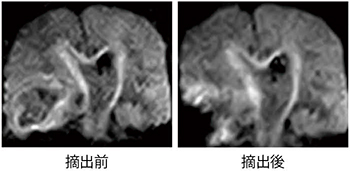

術中DWI

摘出前と摘出後の術中DWI。本画像はAIRIS-Ⅱによるものだが,APERTOを用いてルーチンでの術中DWIによる神経線維の描出をめざす。